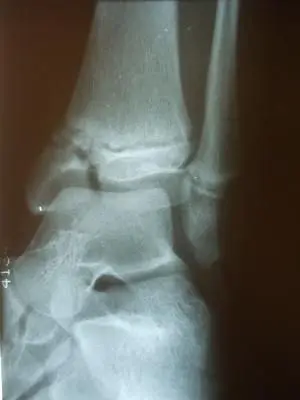

Post- surgical repair of the injury with screws traversing the injured area to allow good reduction and healing without affecting active growth plate areas.

These are post-operative x-rays after repair of the fracture using screws that remain permanently in most cases but does not cross the growth plate to allow healing of the fracture without affecting the growth of the leg bone. Bone healing typically takes 6-8 weeks.